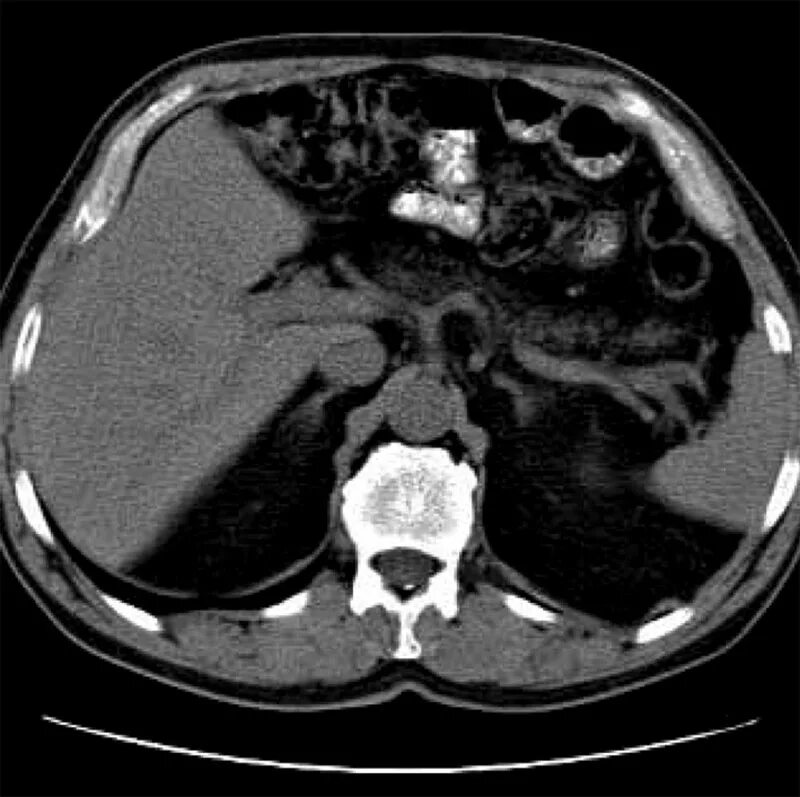

Диффузные изменения поджелудочной железы стеатоз